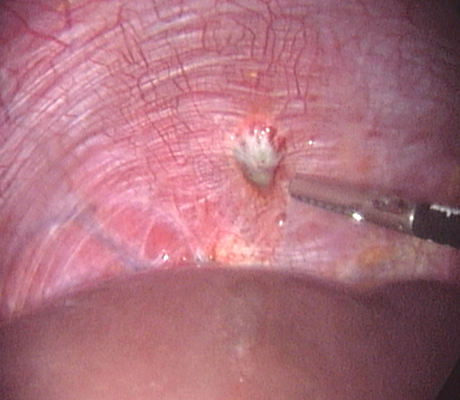

Diagnosis of endometriosis can only be done with certainty through a laparoscopy. Although this means surgery, a patient can also be treated at the same time, saving an extra procedure and the associated risks.

Laparoscopy is an operation (keyhole surgery) conducted under general anaesthesia. A telescope is introduced into a small incision in your navel, other small incisions are made for using special laparoscopic instruments and all the pelvic organs are examined with magnification (Video-laparoscopy) ; then the endometriosis is treated. Video Laparoscopy allows conservative surgery (hysterectomy is NOT the usual treatment for endometriosis) which means laparoscopic excision of the endometriotic implants, with restoration of the normal anatomy and preservation of the uterus, tubes and ovaries.

There is plenty of evidence that laparoscopic excisional treatment improves fertility, even in mild cases of endometriosis.

There are a number of ways as endometriosis may cause infertility. Although women with mild endometriosis may get pregnant, endometriosis is usually a progressive disease, as it gets worse with time. So early diagnosis and treatment is important. Women with advanced disease have low chance of achieving a spontaneous pregnancy. There is plenty of evidence based medicine showing that laparoscopic treatment of endometriosis does improve fertility. When a patient has an ovarian endometriotic cyst associated with infertility, laparoscopic surgery is the first line of treatment. The average pregnancy rate reported after surgery in these cases is 35-50%. So laparoscopic surgery provides a woman with good chances of becoming pregnant spontaneously.